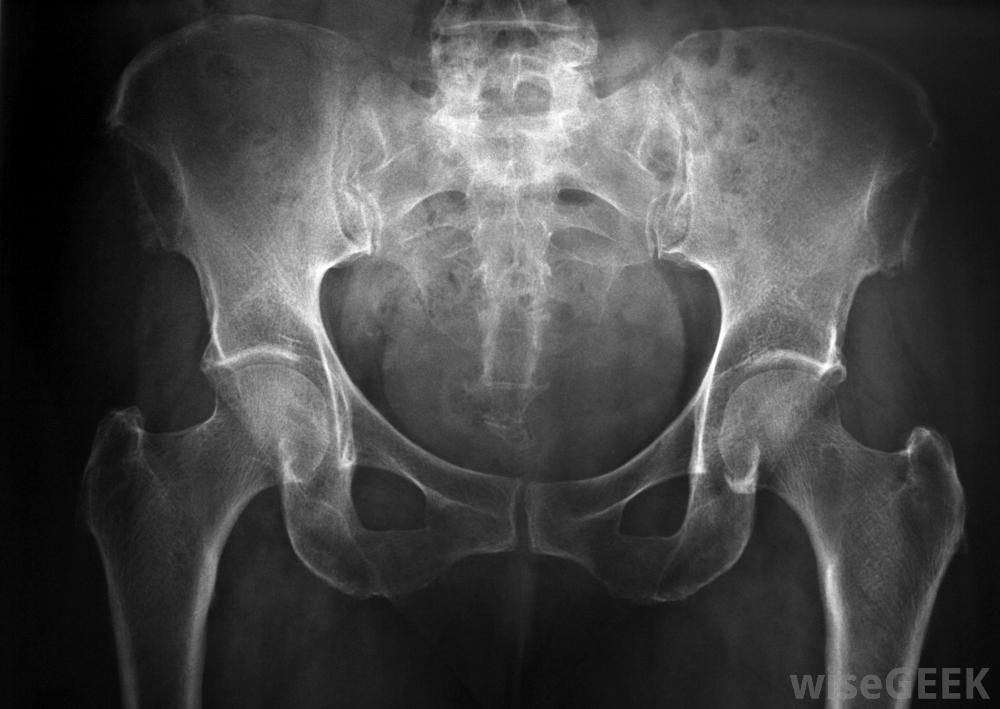

髋部最大的骨头。由左右半部分组成,共同构成翼形骨盆带。髂嵴是髂骨每侧的上弯曲部分。髂骨表面积大,是收集用于髂骨移植的骨的有利位置。

手术前后对需要移植物的区域进行X光检查。

采集和植入髂骨嵴移植物是一种外科手术,由矫形外科医师进行。病人需要全身麻醉,需要在医院呆几天。这个过程包括两个步骤手术部位,一个位置用于修复骨骼,另一个位置用于采集髋部的骨骼。手术前后将要求对需要修复的区域进行X光检查,以确保移植骨正确植入。